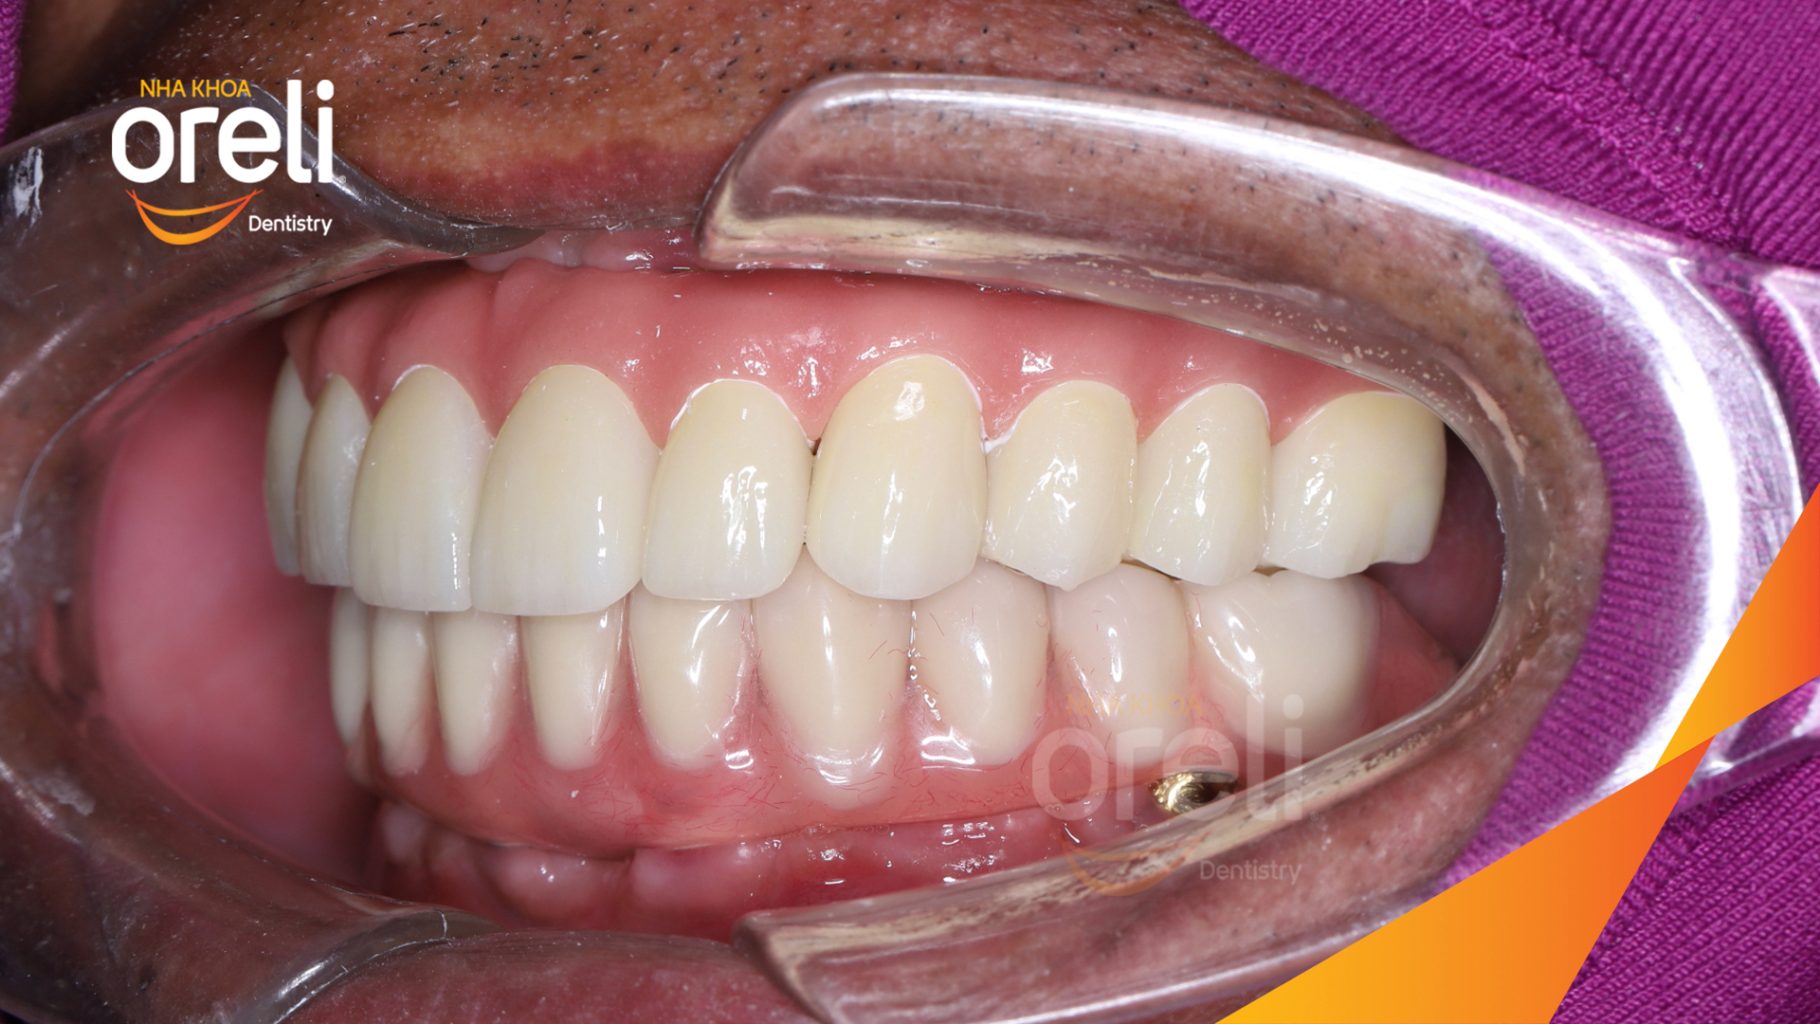

Ca trồng răng implant toàn hàm phục hồi ăn nhai và thẩm mỹ nụ cười. Kết quả thực tế trước và sau điều trị tại Nha khoa Oreli.

Tình trạng: Mất răng toàn bộ hàm trên và hàm dưới

Giải pháp: Trồng răng implant hai hàm với phục hình tạm

Kết quả: Ăn nhai trở lại và nụ cười thẩm mỹ

Hình ảnh thực tế